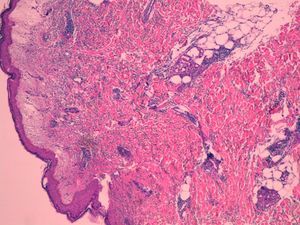

Case ReportThe patient is a 70 years old male with no history of interest, who had recurrent episodes of 2 weeks with high fever, leukocytosis, and erythematous papules and plaques on the extremities, with dense neutrophilic infiltrates in the biopsy (Fig. 1). The patient had asymmetric oligoarthritis affecting the wrist and knees. Analytically, there was an elevated sedimentation rate (ESR), leukocytosis, and anemia. Episodes were treated with glucocorticoids at 0.5mg/kg, with little response. The disease became chronic and recurrent. Indomethacin was prescribed a dose of 150mg/day and potassium iodide was added, without improvement. In parallel, the patient was diagnosed with a type 1 RABE after the study of persistent anemia. We performed multiple red blood cells transfusions.